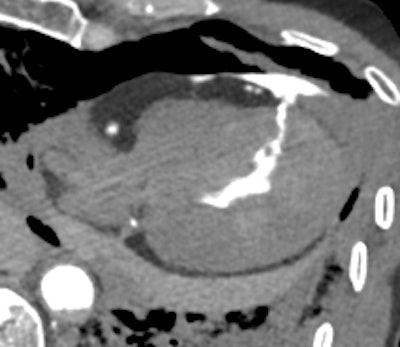

Postmortem CT reveals a large-volume hemopericardium caused by myocardial rupture, providing a definitive cause of death and avoiding the need for an invasive autopsy. All images courtesy of Drs. Susan Shelmerdine and Natasha Davendralingam.

Postmortem CT with coronary angiography and positive contrast highlights the precise location of myocardial rupture within the left ventricular wall, showcasing the value of contrast-enhanced imaging in providing accurate diagnoses without the need for autopsy.